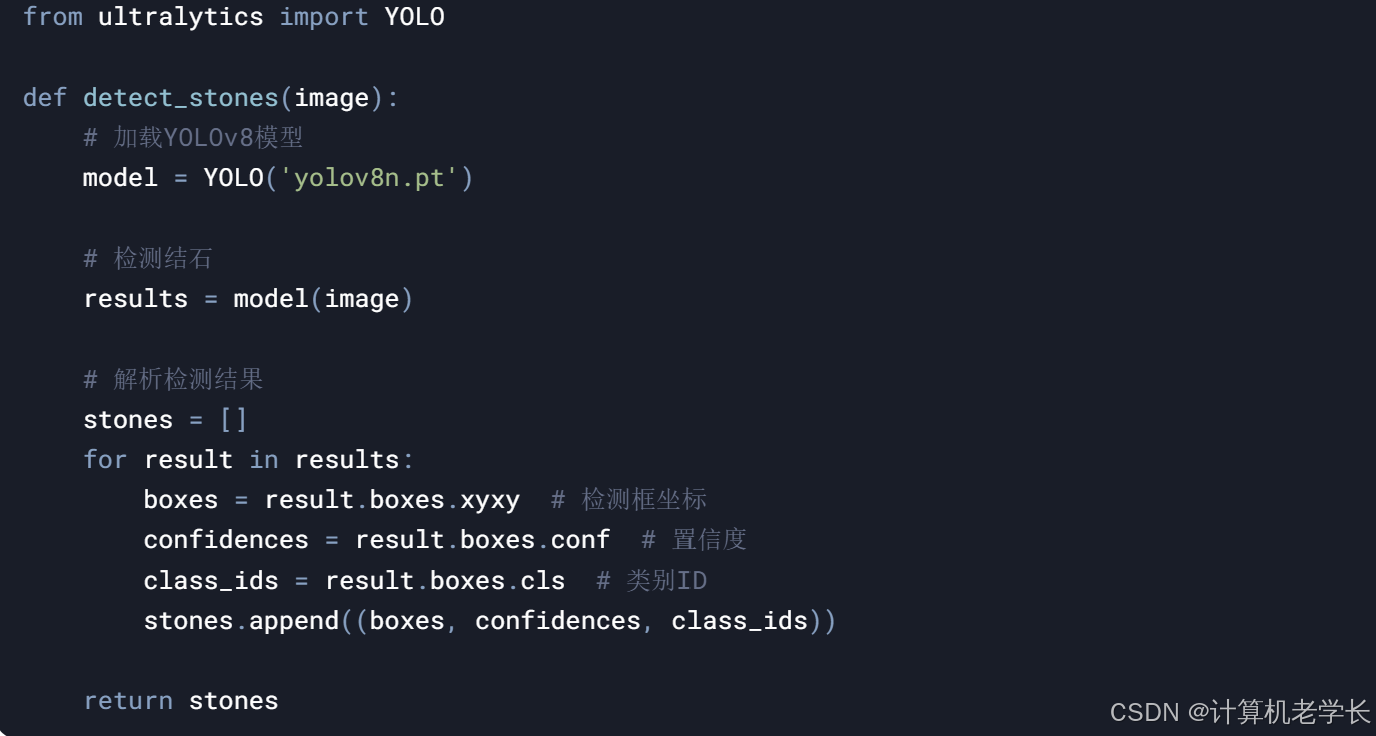

3.2.6 结石检测模块

结石区域定位

YOLOv8模型

4.3 结石检测